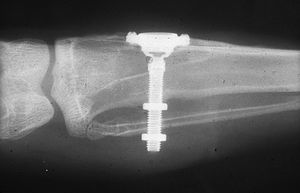

While studying bone cells in a rabbit femur using a titanium chamber, Branemark was unable to remove it from bone. His realization that bone would adhere to titanium led to the concept of osseointegration and the development of modern dental implants. The original xray of the chamber embedded in the rabbit femur is shown (made available by Branemark).

In the 1950s research was being conducted at Cambridge University in England to study blood flow in vivo. These workers devised a method of constructing a chamber of titanium which was then embedded into the soft tissue of the ears of rabbits. In 1952 the Swedish orthopaedic surgeon, Per-Ingvar Brånemark, was interested in studying bone healing and regeneration. During his research time at Lund University he adopted the Cambridge designed "rabbit ear chamber" for use in the rabbit femur. Following the study, he attempted to retrieve these expensive chambers from the rabbits and found that he was unable to remove them. Brånemark observed that bone had grown into such close proximity with the titanium that it effectively adhered to the metal. Brånemark carried out further studies into this phenomenon, using both animal and human subjects, which all confirmed this unique property of titanium.